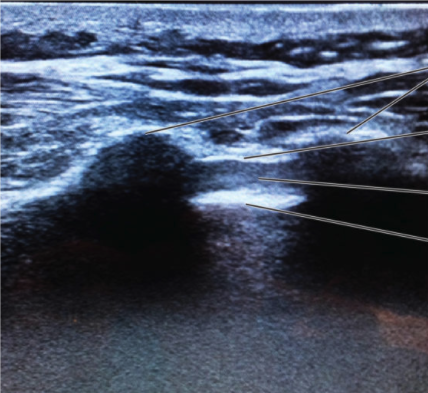

Identify the following block and structures